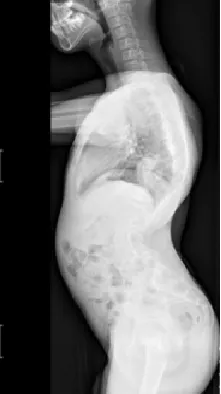

▷特发性脊柱侧凸

特发性脊柱侧凸是所有脊柱侧凸中最多见的,原因不明。其中青少年特发性脊柱侧凸(AIS)最常见,发病率1.5%-3%,占全部脊柱侧凸的75%-80%。约80%的AIS患者需佩戴支具以控制侧凸进展,佩戴支具的患者中,约1/4最终需要手术治疗。

▲ 女,12岁,特发性脊柱侧凸、先天性脊柱畸形

▲ 女,14岁,青少年特发性脊柱侧凸